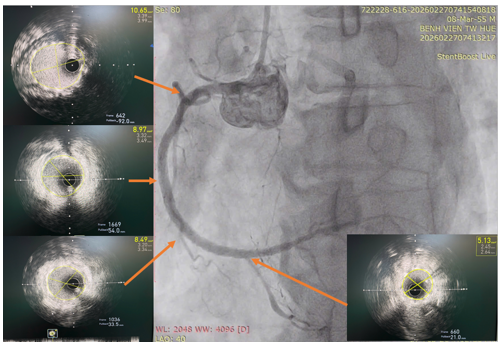

Sau khi can thiệp cấp cứu LAD, bệnh nhân được tiến hành can thiệp trì hoãn tiếp theo nhánh RCA dưới sự hướng dẫn của siêu âm nội mạch (IVUS) (hình 4 và hình 5). Bệnh nhân sau đó ổn định và ra viện sau một tuần điều trị.

Hình 5. Hình ảnh IVUS sau can thiệp với kết quả Stent nở tốt, áp sát thành mạch với diện tích lòng mạch lần lượt là 5,13 mm2, 8,49mm2; 8.97 mm2; 10,65 mm2 từ đoạn xa đến đoạn gần.